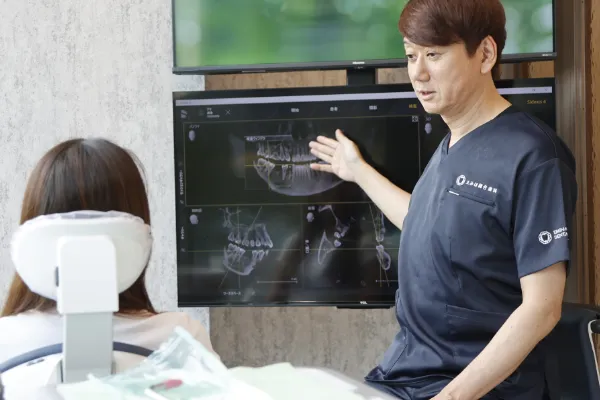

私は口腔外科専門医歴20年以上の経験と技術で、

「痛くない・早い・丁寧な治療」を心掛け、学会、研修会、スタディーグループなどで最新の技術を習得し、

患者様に安全・安心のインプラント治療を行っています。

しかし、インプラント治療だけをすることがが全てではありません。

患者様にとって何がベストな治療なのかじっくりと話して判断するとともに、

患者様の意思を尊重して治療をおこないます

ので、

嫌な思いや我慢をすることがないように、誠心誠意つとめます。

インプラントで好きなものを食べられる幸せを再び感じてください!

えみは総合歯科のインプラント治療は、CTスキャンで口腔内の3Dモデルを作成し、コンピュータシステム「ビオナ」を使用して歯の状態を正確に解析・診断します。

専門医とコンピュータから、精密なインプラント挿入の治療計画を作成します。機械技術と医師の腕が合わさり、患者様の手術への不安や負担を軽くして、手術(インプラント埋め込みの位置・角度)の誤差も従来のものと比べて格段に下がり、ミリ単位の誤差に抑える安全正確な手術になっています。